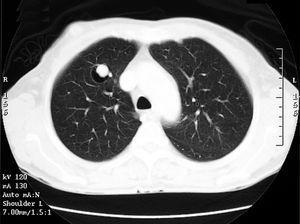

Mujer de 69 años, remitida a nuestro servicio para el estudio de un nódulo pulmonar. La paciente no refería hábitos tóxicos y como único antecedente de interés destacaba el diagnóstico de diabetes mellitus tipo 2, habiendo requerido un ingreso hospitalario por coma hiperglucémico. Cuatro meses antes del ingreso había presentado un episodio de hemoptisis autolimitado. En la radiografía de tórax se objetivó un nódulo pulmonar de unos 2 cm de diámetro en el lóbulo superior derecho, de bordes lisos y bien delimitado, presente en una radiografía previa practicada 6 meses antes, aunque de menor tamaño. No existían hallazgos destacables en la exploración física. La analítica y el electrocardiograma realizados al ingreso no presentaban alteraciones. Se realizó una fibrobroncoscopia sin objetivarse alteraciones macroscópicas. La microbiología y citología del broncoaspirado no evidenciaron hallazgos patológicos. En un nuevo control radiológico practicado un mes más tarde no se observaba el nódulo pulmonar. Sin embargo, en la tomografía computarizada de tórax se demostró la existencia de una imagen nodular, de 1,5 cm de diámetro máximo, en el lóbulo superior derecho. Esta imagen captaba contraste de forma muy significativa (similar a la captación de vena y arteria pulmonares), lo que hizo sospechar que su origen fuera vascular. La lesión estaba situada en el interior de una bulla de 2 cm de diámetro (fig. 1). Se realizaron pruebas funcionales respiratorias que no objetivaron alteraciones significativas: capacidad vital forzada (FVC) de 2,06 l (85% ref.), volumen espiratorio forzado en el primer segundo (FEV1) de 1,94 l (109% ref.), FEV1/FVC del 94% y capacidad pulmonar total de 4,30 l (93% ref.). La gasometría arterial respirando aire ambiente mostró: pH de 7,41, presión arterial de oxígeno de 87 mmHg y presión arterial de anhídrido carbónico de 38 mmHg. Se realizó gasometría arterial respirando con oxígeno al 100%, que mostró los siguientes valores: pH de 7,44, presión arterial de oxígeno de 601 mmHg y presión arterial de anhídrido carbónico de 35 mmHg. La fracción de mezcla venosa (Qs/Qt) calculada a partir de estos valores fue del 4%. Se practicó una arteriografía pulmonar en la que no se encontraron alteraciones ni en las arterias pulmonares en sus ramas de bifurcación ni en la circulación arterial intraparenquimatosa. Sin embargo, en la fase venosa del estudio se evidenció una dilatación de morfología sacular que dependía de una rama venosa del segmento apical del lóbulo superior derecho (fig. 2). Se realizó una aortografía torácica en la que no se evidenció conexión con la circulación sistémica, por lo que se descartó irrigación mixta de la dilatación. La arteriografía bronquial selectiva tampoco demostró alteraciones significativas. Se realizó ecocardiograma que descartó cualquier tipo de valvulopatía u otro tipo de enfermedad cardíaca. Dada la ausencia de repercusión clínica, hemodinámica y gasométrica de dicha malformación vascular, se decidió no practicar ningún tipo de intervención y se dio de alta a la paciente, sin que haya presentado complicaciones posteriores.

Fig. 1. Tomografía computarizada de tórax donde se objetiva una imagen nodular en el lóbulo superior derecho que capta contraste y es indicativa de un origen vascular; la anomalía se halla situada en el interior de una bulla.